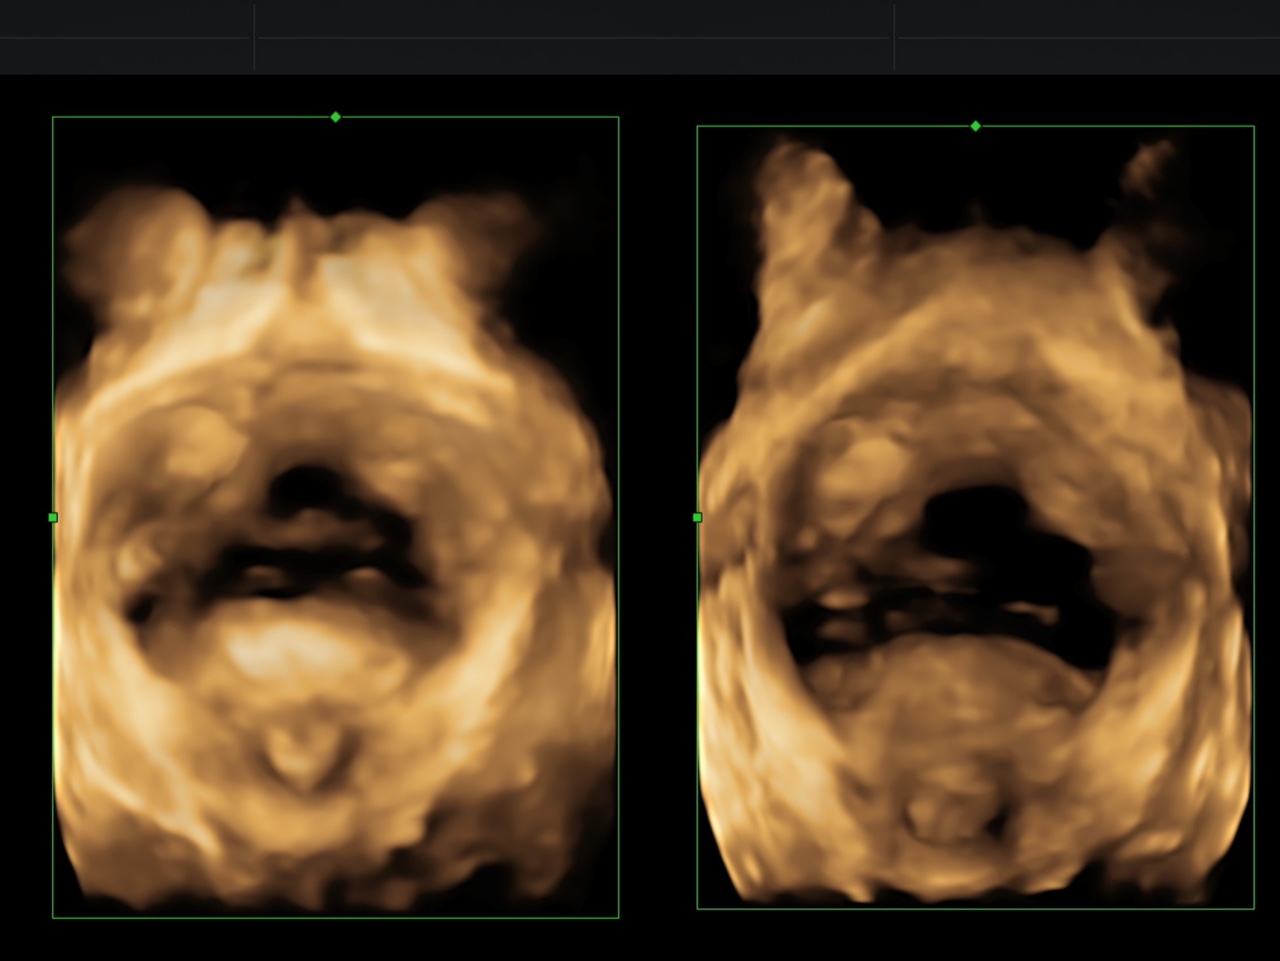

左圖,靜息狀態(tài),右圖,Valsalva動狀態(tài)盆膈裂孔面積增大

?動態(tài)成像:實時觀察盆底肌肉、韌帶在靜息、收縮、用力狀態(tài)下的運動軌跡,精準定位損傷部位;

?量化評估:通過三維重建技術,測量裂孔面積、器官位置等關鍵數(shù)據,科學判斷盆底功能。